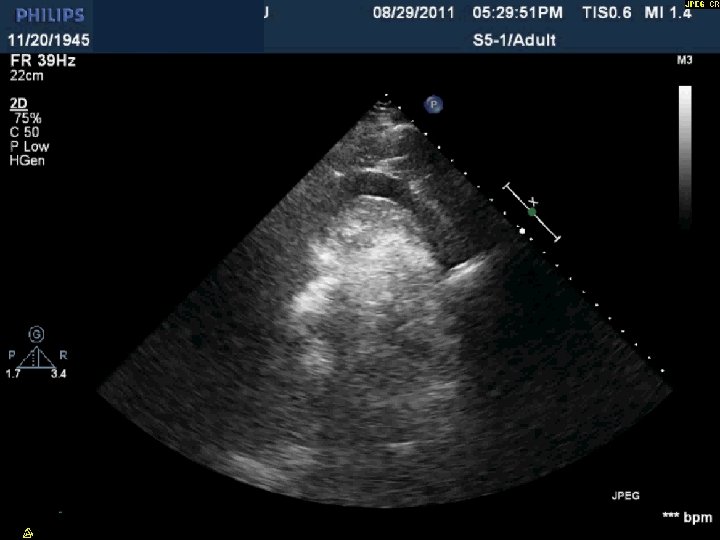

Coronary Perforation Methods of Patient Management • Dual Catheter (‘Ping Pong’) Technique • Prolonged balloon inflation and covered stents • Reversal of anticoagulation — Know contradictions to protamine sulfate for UFH; Avoid bivalirudin, LMWH — Reserve GP 2 b 3 a inhibition until successful crossing and wire change-out Embolization • — Coil, gelfoam, methacrylate, autologous blood/fat • Microcatheter Occlusion • Confirmation of successful management — Contralateral injection — Right heart catheterization — Echocardiogram — Contrast echocardiography

Day 2 No further pericardial drainage, echo without effusion…pericardial catheter pulled Day 3 Enoxaparin for DVT prophylaxis initiated 8 hours later, PEA arrest Echo shows recurrence of effusion and tamponade physiology

Day 2 Stable overnight No further pericardial drainage Echo shows no recurrence of effusion In ICU, pericardial pigtail catheter pulled…. . Within 5 minutes, systolic blood pressure drops to <80 and bedside echo confirms recurrence of effusion Emergency pericardiocentesis draws off 650 cc immediately followed by continuous drainage of blood